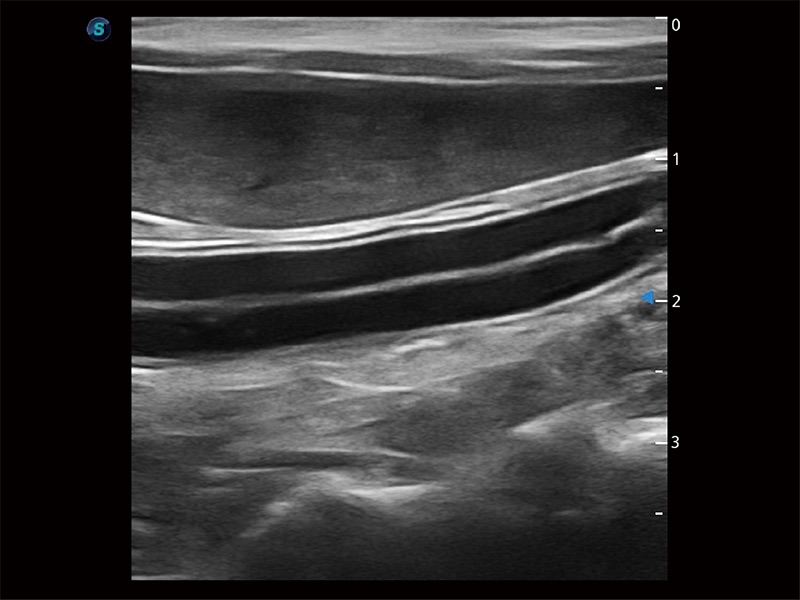

(犬)肠道

(犬)肾脏显微血流